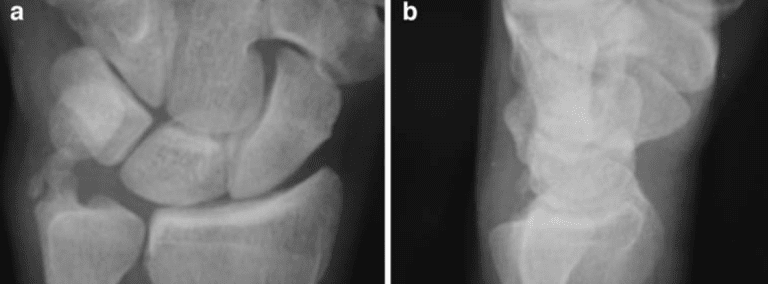

Carpal instabilities continue to be a controversial topic in hand surgery. Accurate diagnosis of the ligament injuries is usually difficult without an arthroscopic evalu-ation. Few studies have focused on the diagnosis and proper management of simultaneous scapholunate (SL) and lunotriquetral (LT) ligament tears. This is an uncommon injury that leads to marked disability and chronic wrist pain. This is essentially a “floating lunate” and indicates a severe ligamentous lesion. Thirteen patients (six female and seven male) with complete SL and LT tears and with gross arthroscopic dynamic carpal instability were included in the present study. None of the patients showed radiographic evidence of lunate dislocation. One patient presented acutely and was operated on 3 days after the injury. The average time from the initial injury to the arthroscopy for the other 12 patients was 13.5 months (range 1.5–84 months). All patients underwent arthroscopic debridement of the SL and LT ligaments coupled with percutaneous pinning (two 0.045-in. Kirschner wires) in both joints. At the final follow-up, the average range of motion was 50°of flexion, 54° of extension, 77° of pronation, 80° of supination, 25° of ulnar deviation, and 15° of radial deviation. The average final grip strength was 67% from the non-affected side. All patients had negative shifting tests at final follow-up. Furthermore, there was no evidence of any static or dynamic instability in all the patients except for one patient who developed a volar intercalated segment instability 8 months after the surgery. At the final follow-up, ten patients had no pain, one had mild pain, and two experienced moderate pain.